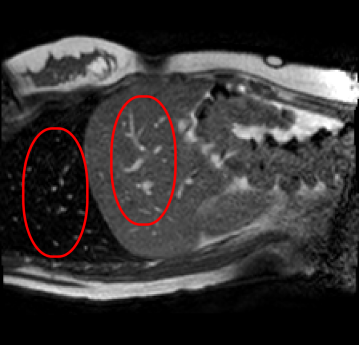

Qualitative results are shown in Fig. 4. We observe no large qualitative differences in the performances of MFIN and MFINc for either loss function. Since, MFINc-SSIM provides the best quantitative results, we show interpolated images from this method and compare them against SCIN-SSIM. Both methods perform well when the motion between the neighbouring images is low. This is reflected in the absence of any structures in the error images in Fig. 4.1. However, RMSE is lower for SCIN because it produces a denoised interpolated image, while MFIN carries over the noise pattern from the neighbouring known image. Whenever there exists high motion between the images being interpolated, SCIN produces blurry images and often misses image structures. This can be observed in cases 2-4 in Fig. 4. For all these cases, MFINc (and also MFIN) produces sharp images and largely preserves structures in the images. Fig. 4.2 shows a case where MFINc additionally has a much better performance with respect to image alignment. Fig. 4.3 shows a representative case, with small improvement in image alignment, yet worse RMSE and SSIM values for MFINc. Finally, Fig. 4.4 shows a case, where MFINc produces worse alignment of structures than SCIN.

Figure 3: Ground truth images (a), SCIN-SSIM results (b) and difference images (c), MFINc-SSIM results (d) and difference images (e). Rows: (1) low motion case, (2)-(4) high motion cases, where MFINc produces (2) much better, (3) slightly better and (4) worse structure alignment that SCIN. (RMSE, SSIM) pairs are indicated over the respective errors images.